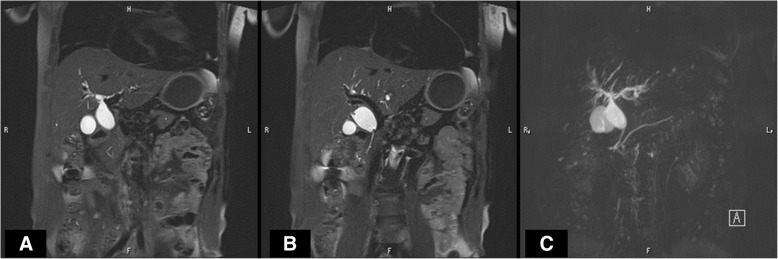

A 67-year-old man was found to have a dilatation of the common bile duct (CBD) (19 mm) during a medical examination at 62 years of age. The dilatation of the CBD subsequently progressed (26 mm), and he was admitted to our hospital for surgical treatment. Abdominal computed tomography revealed a dilatation of the CBD with no tumor or stone. Magnetic resonance cholangiopancreatography revealed a dilatation from the common hepatic duct (CHD) to the middle bile duct (Fig. 1a and b) with PBM (Fig. 1c). Endoscopic retrograde cholangiopancreatography (ERCP) from the papilla of Vater revealed the pancreatic main duct via the pancreatic branch duct (Fig. 2a and b). PBM with dilatation of the CBD (26 mm) and incomplete PD were revealed (Fig. 2c). Figure 3 shows a schema of this case with dilatation of the CBD and PBM, and incomplete PD in which the ventral pancreatic duct joined the dorsal pancreatic branch duct was observed.